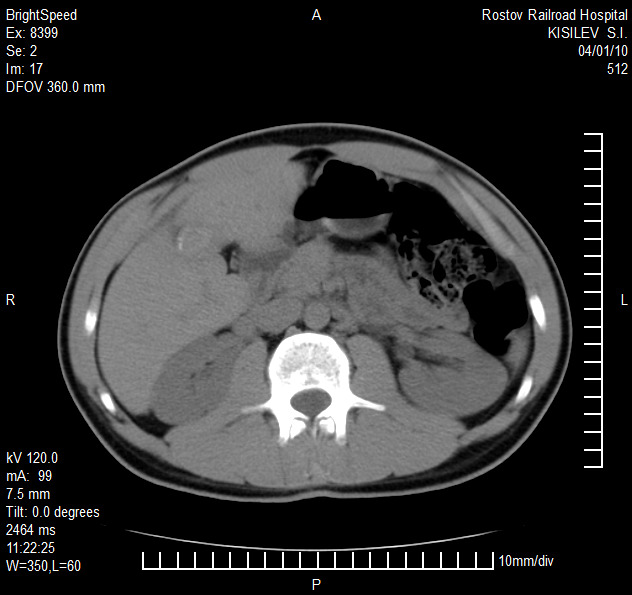

Представлены клинические наблюдения редкого осложнения эхинококкоза печени – прорыва эхинококковой кисты в желчные протоки. Осложнение стало причиной обструкции желчных протоков, механической желтухи и холангита. Освещены этапы диагностики, роль УЗИ в выявлении осложнений эхинококкоза печени, рассмотрены способы минимально инвазивного лечения с применением эндоскопических и чрескожных технологий под контролем лучевых методов.